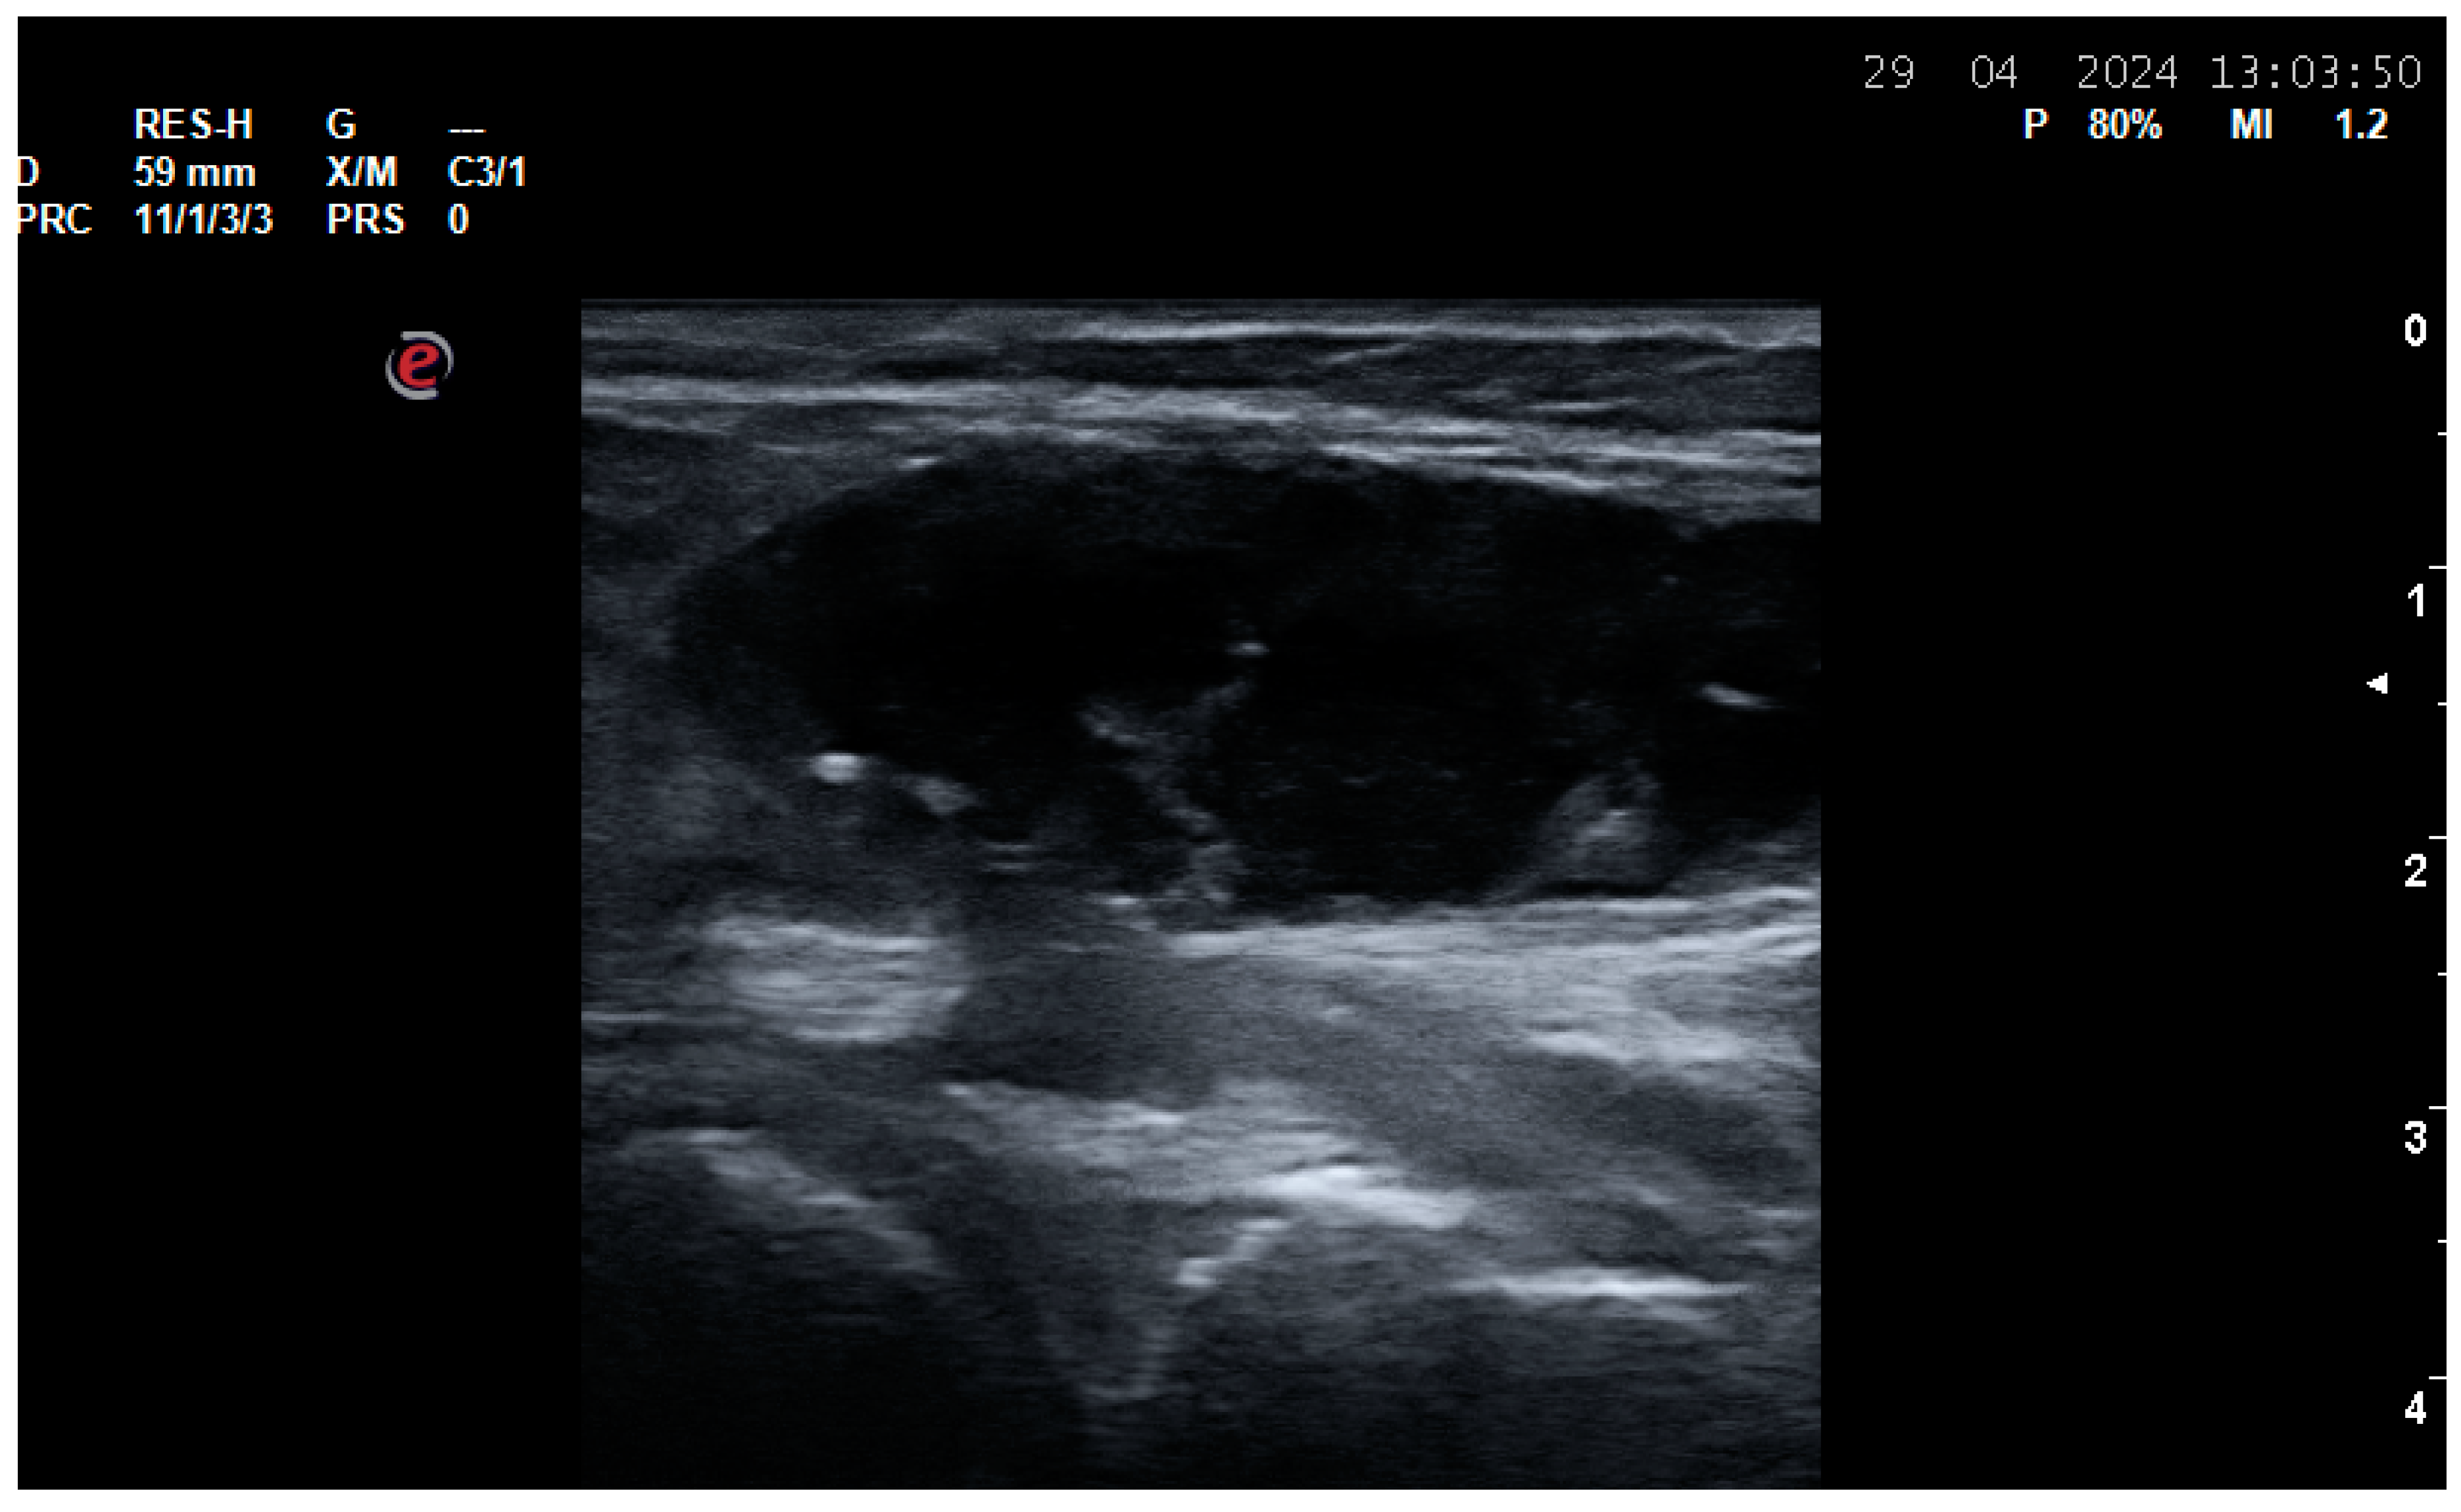

3.1. US Use in Patients with Osteoarthritis (OA)